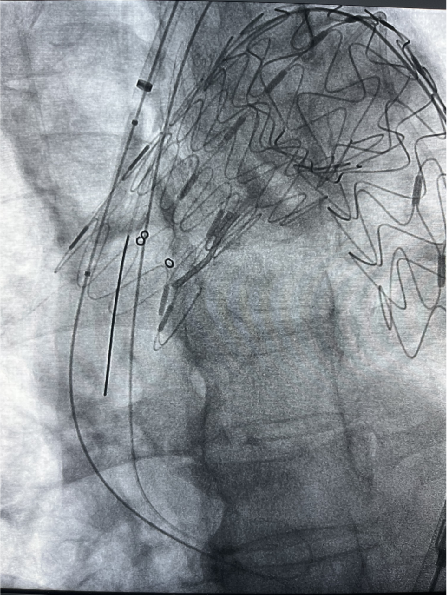

患者男性,78岁,胸主动脉瘤,采用双开窗技术(LSA+LCCA)重建分支。Futhrough系统在直径较小的血管中(成角小、行程长)实现精准穿刺,术后12个月随访显示支架通畅,无内漏或移位。

case 3

III型弓合并长段动脉瘤病变,LSA开口位于瘤体且与主动脉弓夹角小,病变累及长度长,手术截瘫风险高。

传统开窗技术因血管成角小、路径迂曲难以精准定位。

通过三开窗技术(LSA+LCCA+其他分支)完成重建,Futhrough系统的高顺应性和行程控制能力有效避免了血管损伤,术后截瘫风险显著降低。